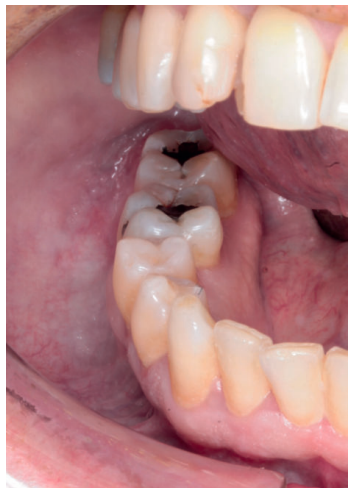

Acudió a servicio de cirugía oral, derivado por su odontólogo, un paciente varón de 65 años sin antecedentes médicos de interés, tras comprobar un importante crecimiento de una imagen radiotransparente respecto a última radiografía de hacía 5 años. El paciente no refirió sintomatología asociada. A la exploración extraoral no se apreció ningún tipo de deformidad ni afectación ganglionar. A la exploración intraoral pese a que se constató la integridad de las corticales, las cuales no estaban abombadas, sí que se pudo apreciar a la palpación un signo positivo de Dupuytren o de “Ping-Pong”. Además se constató una falta de afectación de los dientes del cuarto cuadrante que no presentaban movilidad y tenían una vitalidad positiva (Figura 1). Como complemento a la exploración clínica se solicitó un estudio mediante TAC, donde se apreció la extensión de una lesión radiotransparente que afectaba a rama y cuerpo mandibular derecho. (Figuras 2 y 3).